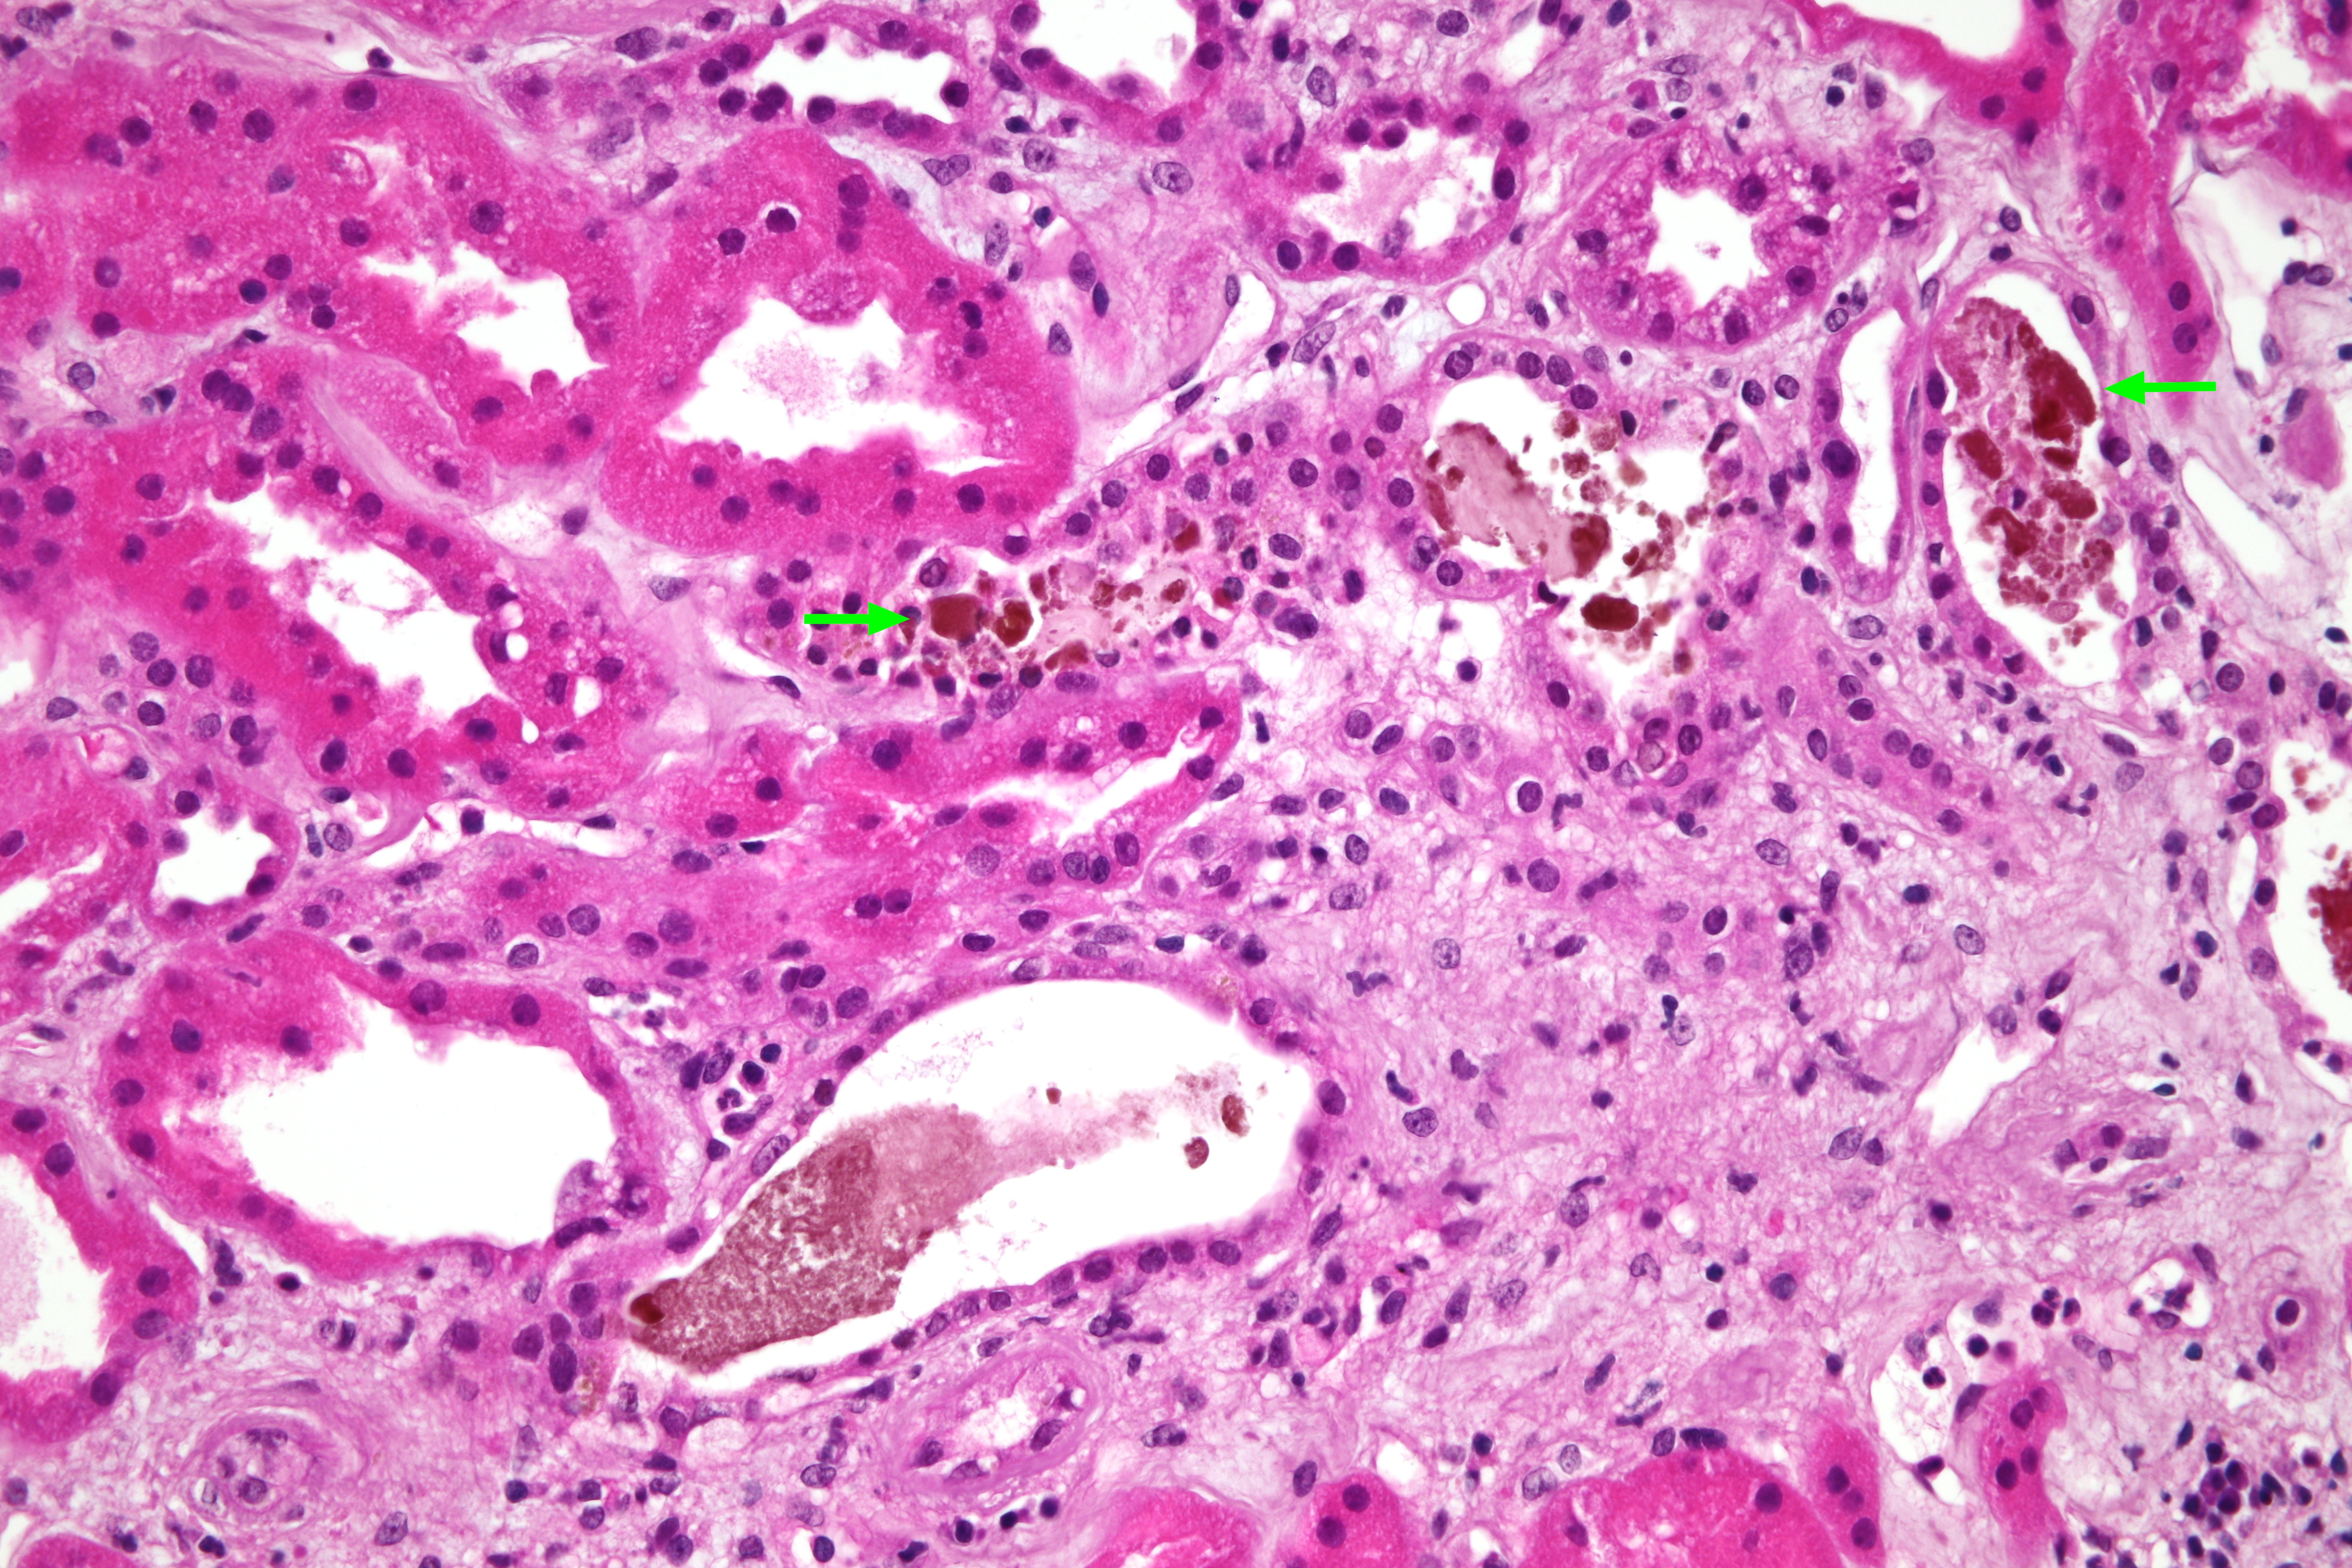

OBR. 1 Bioptický nález, barvení hematoxylinem a eosinem – morfologie akutní tubulární nekrózy, žlučové válce v tubulech označené šipkami.

Zde byl doplněn základní imunologický screening s negativním nálezem, vyjma hodnoty C3 složky komplementu lehce snížené na 0,87 g/l. Následně jsme proto provedli renální biopsii, v níž dominovala morfologie akutní tubulární nekrózy (ATN) s četnými žlučovými válci v tubulech a projevy intrarenální obstrukce s akumulací Tammova–Horsfallova proteinu v intersticiu (obr. 1 a 2). Bioptický nález byl tedy uzavřen jako obraz cholemické nefrózy. Třetí den po renální biopsii vzhledem k dalšímu nárůstu hodnot dusíkatých katabolitů a při známkách hyperhydratace byla zahájena intermitentní hemodialýza. Celkem jsme provedli pouze dvě procedury, jelikož záhy došlo u pacienta k obnově renálních funkcí a k rozvoji mírné polyurické fáze renálního selhání. Desátý den od biopsie byl pacient v dobrém klinickém stavu propuštěn. Při poslední ambulantní kontrole dva měsíce od propuštění přetrvává elevace hodnot kreatininu 110 µmol/l, bilirubin i jaterní enzymy jsou již v normě.